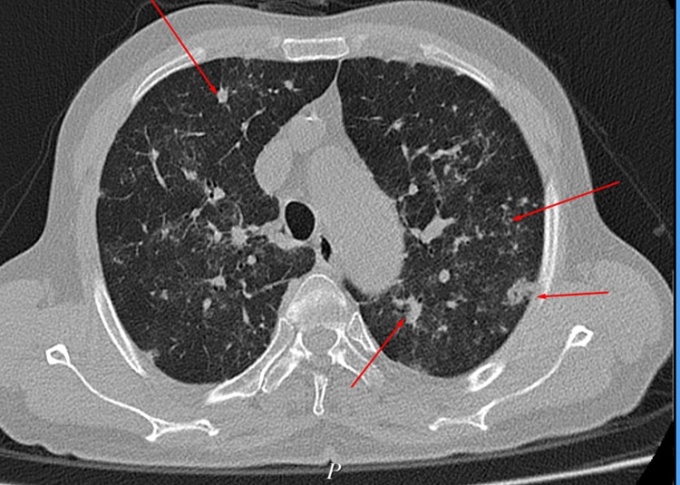

Ngày 9/4, bác sĩ Bệnh viện Đa khoa Hùng Vương (Phú Thọ) cho biết, kết quả chụp CT lồng ngực bệnh nhân cho hình ảnh phổi đông đặc, tổn thương lan tỏa hai phổi do di chứng Covid. Bệnh nhân đang được điều trị tích cực và theo dõi sát tình trạng tổn thương phổi.

Trước đó, người đàn ông này cho biết trong thời gian mắc Covid-19 chỉ có các triệu chứng nhẹ, khỏi bệnh nhanh. Tuy nhiên, di chứng hậu Covid-19 ở phổi của trường hợp này rất nặng.

Từ đây, bác sĩ khuyến cáo F0 sau khỏi bệnh nếu có các triệu chứng bất thường cần đi khám hậu COVID-19 càng sớm càng tốt để dự phòng các nguy cơ, có phương hướng điều trị phù hợp và kịp thời. Đặc biệt, những người thuộc nhóm đối tượng sau đây cần lưu ý: